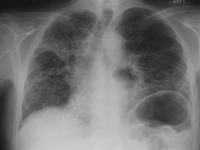

CXR of chronic beryllium disease

From the personal collection of Kenneth D. Rosenman, Michigan State University